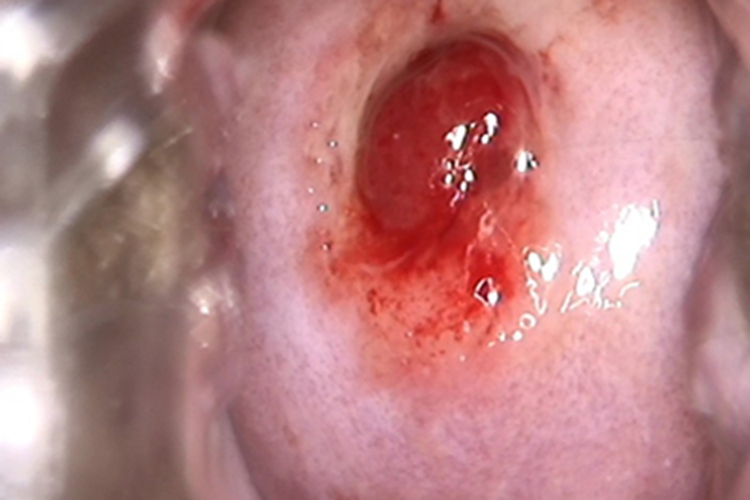

宫颈息肉检查可见患者宫颈口出现大肉球样增生,呈类圆形,颜色为鲜红色,质地比较柔软,表面光滑,有血液渗出,体积过大时会堵塞宫颈。